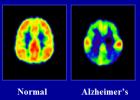

Yapılan ortak bir araştırma ile Alzheimer hastalığının nedenleri arasında havada bulunan kirletici parçacıkların olduğu belirlendi.